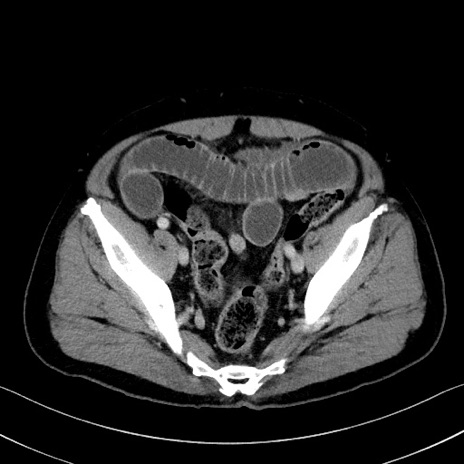

症例35(横断像)

【症例】70歳代 男性

【主訴】腹部膨満、嘔吐

【現病歴】昨日より腹部膨満感出現。本日増悪し、仙痛出現。嘔吐あり、受診。

【既往歴】糖尿病、胆摘後

【身体所見】BP 149/80mmHg、HR 74/min、BT 35.9℃、腹部:膨満、軟、圧痛なし。腸雑音減弱あり。上腹部正中切開瘢痕あり。

【データ】WBC 13500、CRP 1.72